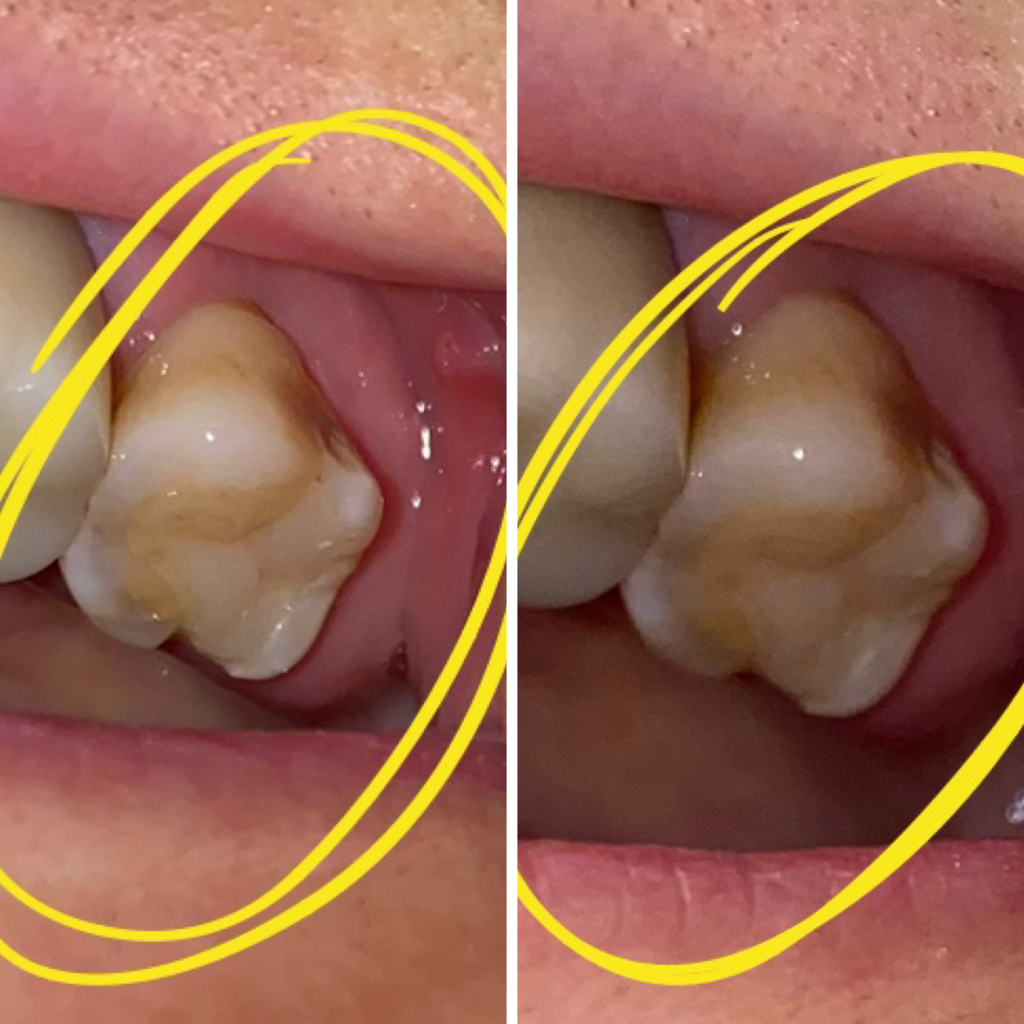

비숑모찌는 힐링힐스 동물치과병원을 방문해 스케일링과 치아검진을 받았습니다. 수술 준비를 하고 있는 모찌와 간호사님~ 마취 후 자세히 살펴보았습니다! 왼쪽 어금니 협측와에 구멍이 났고, 잇몸에 치은종양이 있었고, 오른쪽 어금니의 법랑질이 약간 깨졌으며, 아래 어금니 안쪽 설측와에는 치석이 가득했습니다. 수술 후 치아에 구멍이 난 사진과 강아지의 치은종 사진입니다. 완전히 치유되었습니다. 법랑질이 침식되면 치아의 손상이 더욱 악화되어 파절이 더욱 심해질 수 있으므로 사진과 같은 레진치료가 필요합니다. 아래어금니 안쪽의 설와에도 레진치료를 시행하였습니다. 광고 이후 계속됩니다. 다음 주제 작성자 취소 강아지 치은종/개 치아 구멍/개 수지 치료 – 애견 치과 재생 8 좋아요 0 좋아요 공유 0:00:00 재생 음소거 00:00 00:15 실시간 설정 전체 화면 해상도 자동 480p 자막 비활성화 재생 속도 1.0x(기본) 해상도 자동(480p) 1080p HD 720p HD 480p 270p 144p 자막 설정 비활성화 옵션 글꼴 크기 배경색 재생 속도 0.5x 1.0x(기본) 1.5x 2.0x 알 수 없는 오류가 발생했습니다. 도움말이 음소거되었습니다. 도움말 라이센스 이 영상은 고화질로 재생할 수 있습니다. 설정에서 해상도를 변경해보세요. 자세히보기 0:00:00 접기/펼치기강아지 치은종/강아지 구멍/강아지 레진 치료강아지 치은종/강아지 구멍/강아지 레진 치료 – 강아지 치과#강아지 레진 치료#강아지 치은종#강아지 치아#치아에 구멍 # DogDentistry #AnimalDentistry 치료를 마치고 병원 테라스에서 뛰어다니고 노는 모습이 뿌듯했고 기분도 좋아졌습니다. 오늘 치료는 잘 끝났습니다^^ 튼튼한 치아가 잘 유지되어 다음 정기 검진도 잘 받으실 수 있을 것 같습니다. 예쁜 치아를 직접 만나보시길 바랍니다 🙂 힐링힐스 동물치과의 인스타그램을 방문해 주세요 🙂 힐링힐스 동물치과병원은 인스타그램을 사용하고 있습니다. • 힐링힐스 동물치과병원 프로필은 게시물 607개, 팔로워 327명, 팔로우가 있습니다. Ying 189명, 게시물 607개 – 힐링힐스 동물치과병원 인스타그램 사진 및 동영상 보기(@healinghillsvet) www.instagram.com 반려동물의 치과 진료는 사람만큼 여러 번 치료를 받을 수 없기 때문에 더욱 완전하고 세밀해야 합니다. 소중한 강아지/고양이의 치아를 살리고 성공적인 치과치료를 제공하기 위해 힐링힐스는 휴먼치과 또는 휴먼치과대학병원에서 사용하는 최첨단, 고사양 치과장비를 갖추고 끊임없이 연구하고 노력하고 있습니다. 안전을 최우선으로 생각하여 최고의 결과를 만들어 갑니다. 힐링힐스 동물치과병원 50m NAVER 더보기 /OpenStreetMap 지도데이터 x 네이버(주) /OpenStreetMap Map Controller Legend Real Estate 부동산 면 동시 산오리읍 군, 구, 시, 도 힐링힐스 동물치과병원 9- 경기도 성남시 분당구 동판교로52번길 11 힐링힐스 동물치과병원 힐링힐스 동물치과병원 031-708-0078 경기도 성남시 동판교로 9-11 동판교로 52번- 분당구 분당길 진료시간 : 월~토요일 09:30~18:00 (일요일, 공휴일 휴무) 하루 1~2회 집중수술을 진행합니다! 모든 시술은 방문 전 예약 부탁드립니다 🙂